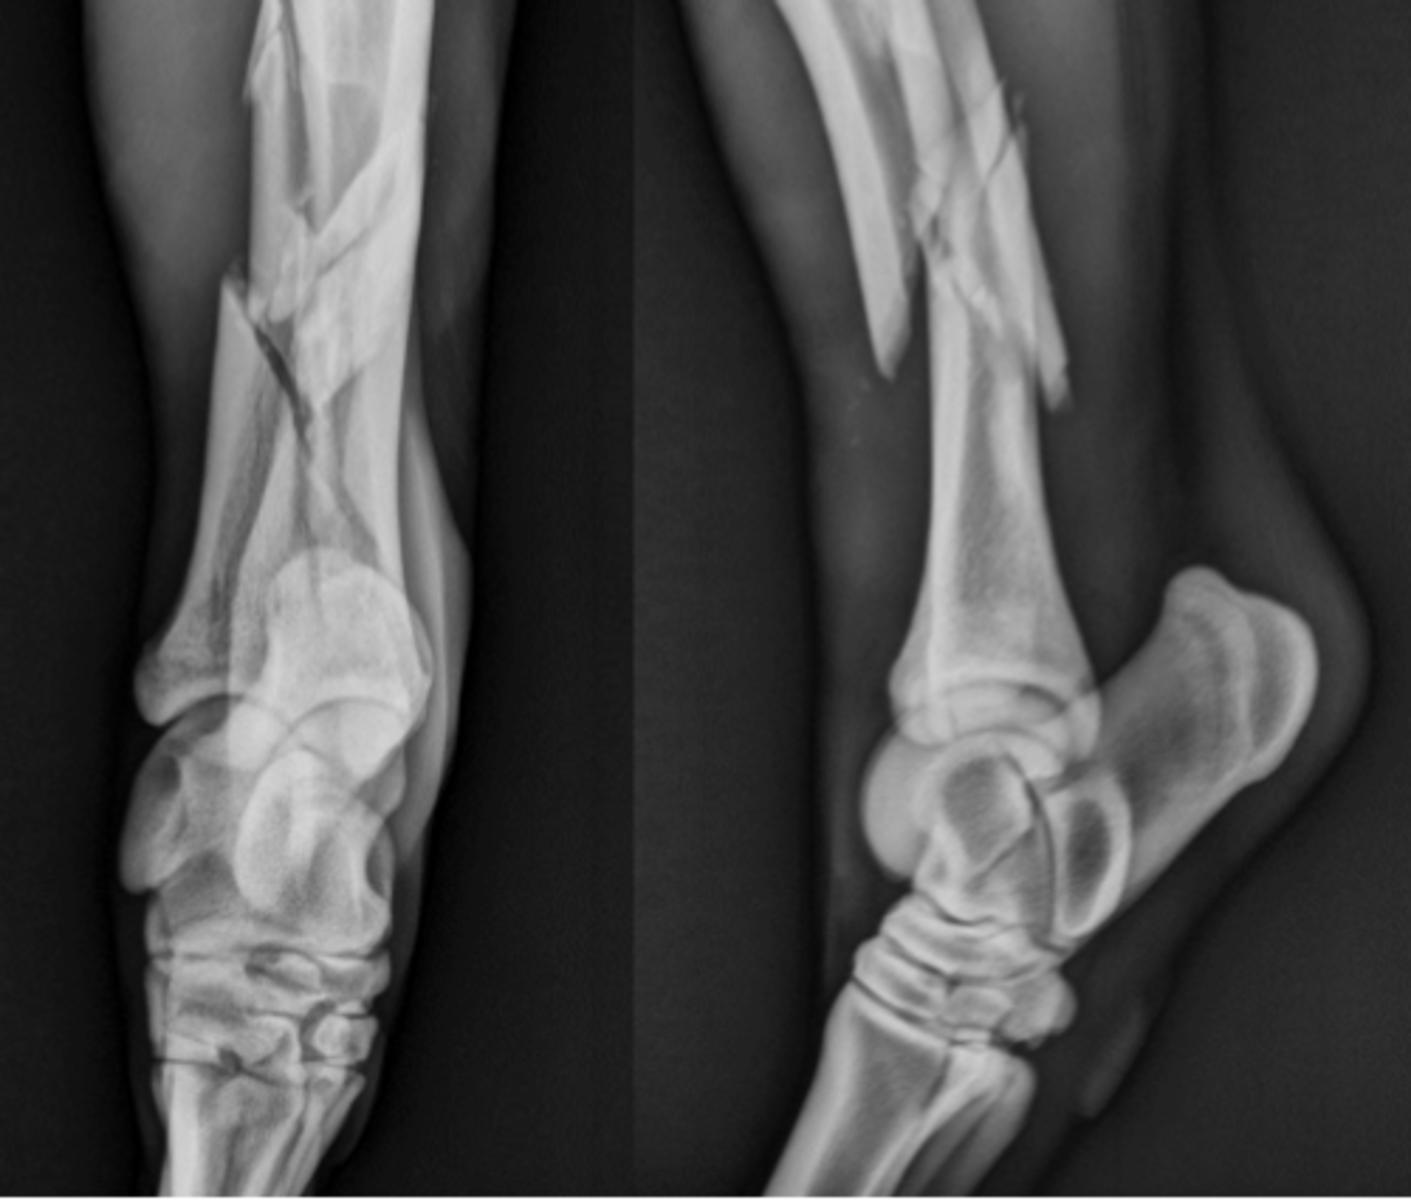

Long bone fracture

What is your top differential for this colt?

Tibia

Which bone is fractured?

Tarsus and stifle

Which joints require immobilization?

Robert jones bandage, lateral splint from the ground to the hip

What is the correct type of coaptation for this tibial fracture?

Internal fixation

How might you treat this fracture?